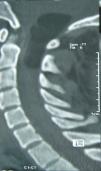

Intradural spinal lipomas with intracranial extension are very rare and are typically diagnosed in childhood. Radical surgical excision usually causes a high rate of morbidity because of the firm adherence between the lipoma and neural tissues. In this report, we present a case of craniocervical intradural intramedullary lipoma in an adult patient. The patient underwent surgery with excision of the mass, leaving a sheet of lipoma on the tumor bed.